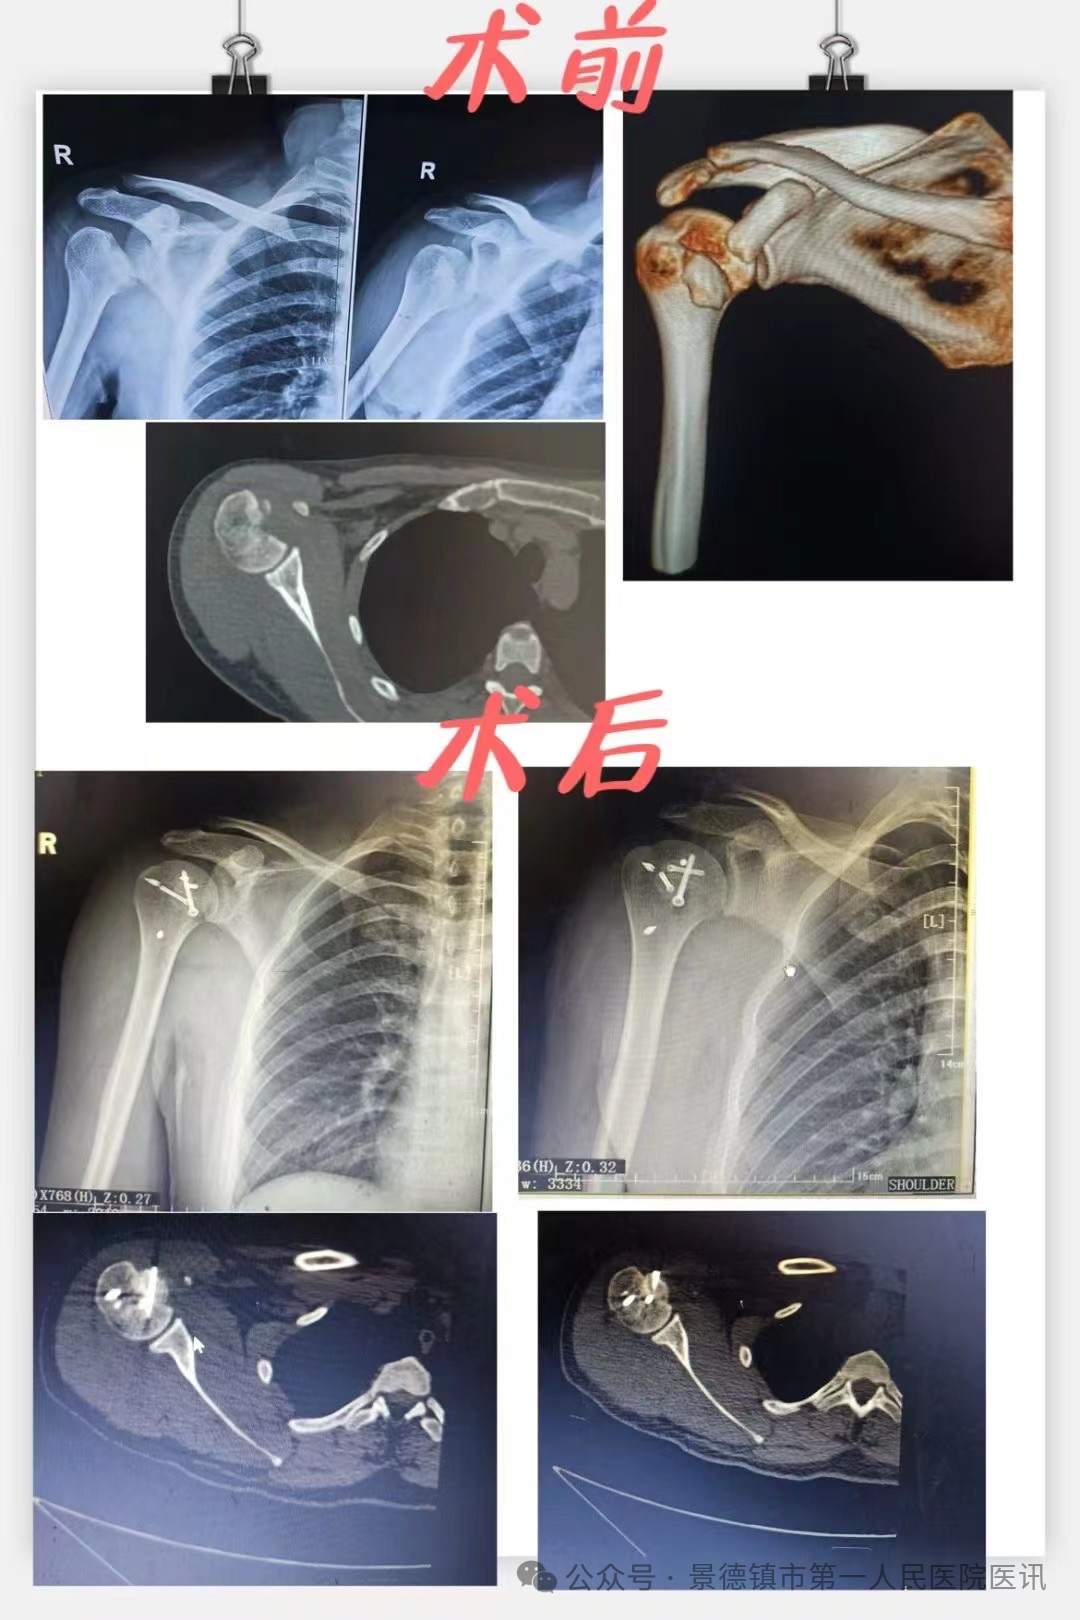

近日,景德镇市第一人民医院骨科收治了一例罕见反Hill-Sachs 损伤患者。患者,30岁,因抽搐时倒地致右肩部受伤,活动受限9天。此前,患者曾在外院被诊断为肩关节后脱位并肱骨头骨折,并在麻醉下予以复位术,但情况并未好转,并且发生了脱位的情况,严重影响了患者的正常生活。

国庆假期第三天下午,骨科主任袁志峰在手术台上接到电话会诊,电话中告知在外院行右肩关节脱位行复位后易发再次脱位的年轻患者即将来求治,结合患者治疗经历和检查报告,骨科团队判断,患者为反Hill一Sachs损伤,合并肱骨小结节骨折、肩袖损伤、肱二头肌长头肌腱损伤。

考虑到患者年轻,肱骨头近1/2破裂,要尽可能重建关节的稳定性,同时又要减少对肱骨头血运的进一步破坏。袁志峰带领刘会文、付裕琪等手术团队反复讨论,大家均认为,手术内固定既要牢固可靠,又要不影响关节活动、减少对关节周围组织的刺激。因此,为患者制定了取髂骨结构性植骨移植+肱骨小结节骨折埋头钉固定+肩胛下肌损伤修复+肱二头肌长头肌腱切断固定的治疗方案。

患者遂于10月4日一早办理入院,急患者所急,并在第二日安排了手术治疗,骨科团队密切配合,为患者成功实施了手术。由于受损关节周围解剖结构复杂,有大量血管、神经通过。术中,手术团队缜密准备、精细操作。术中发现骨折处缺损大,遂切取髂骨用作移植物并夯实,复位肱骨小结节骨折并采取埋头钉固定,受损肩胛下肌予以带线铆钉修复,受损的肱二头肌长头肌腱予以切断并原位固定,历经1.5个小时,手术顺利实施。